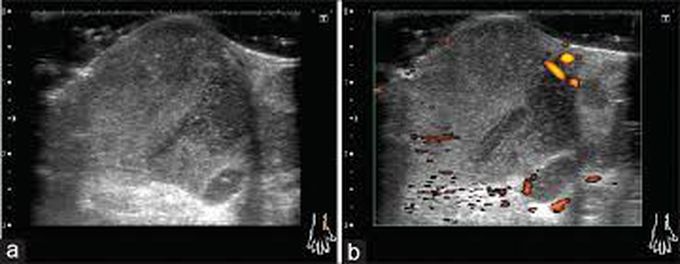

Snowstorm appearance in Ultrasound

When MSU crystals are observed in the synovial fluid, a characteristic musculoskeletal ultrasound appearance of multiple hyperechoic foci floating within the joint cavity is described as a “snowstorm appearance.”